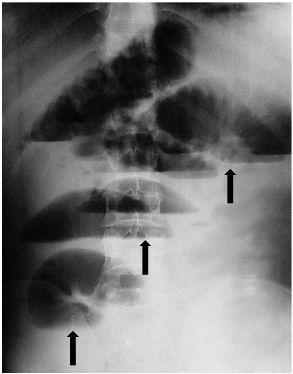

Se trata de un hombre de 46 años de edad, sin antecedentes de intervención quirúrgica, quién acudió al servicio de urgencias por presentar dolor abdominal tipo cólico, náuseas, vómito bilioso frecuente y ausencia de flatos y deposición. A la exploración física se encontró mucosas secas, abdomen distendido, ruidos hidroaéreos aumentados, hipersonoridad difusa a la percusión y ampolla rectal vacía al tacto rectal. La radiografía simple de abdomen en bipedestación, mostró la presencia de niveles hidroaéreos centrales en escalera y distensión de asas yeyunales e ileales (Figura 1).

Figura 1. Radiografía simple de abdomen en bipedestación. Las flechas muestran los niveles hidroaéreos centrales en escalera y la distensión de asas yeyunales e ileales.